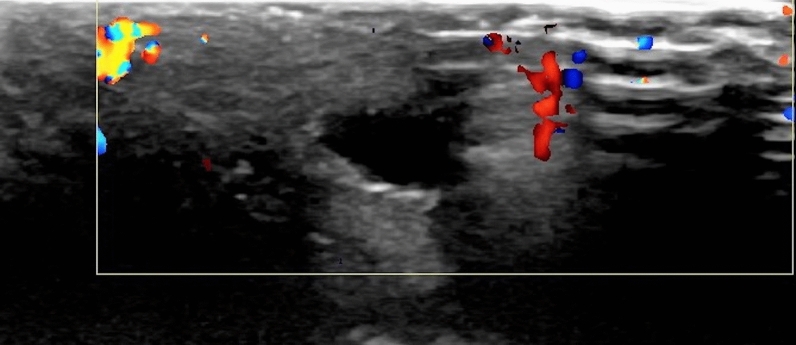

Superficial Doppler ultrasonography revealed dorsal induration consistent with segmental thrombosis of the superficial dorsal vein, suggestive of penile Mondor’s disease (Figs. 1, 2).

Fig. 2.

There was no vascularization at the Doppler ultrasonographic evaluation of the same structure indicating an obstructing thrombus